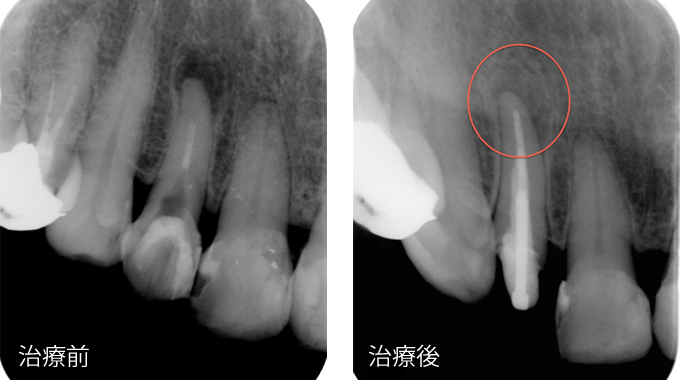

| 精密根管治療症例 |

| 主訴 | 歯茎に出来のもが出来たが、抜かないとダメと言われたので見てほしい |

| 治療内容 | マイクロスコープを用いた精密根管治療による根管治療 |

| 治療期間・治療費 | 治療期間:2ヶ月 ※上記の治療後のレントゲンは2年後のもの 治療費:10万円(税別)他支台築造除去料 |